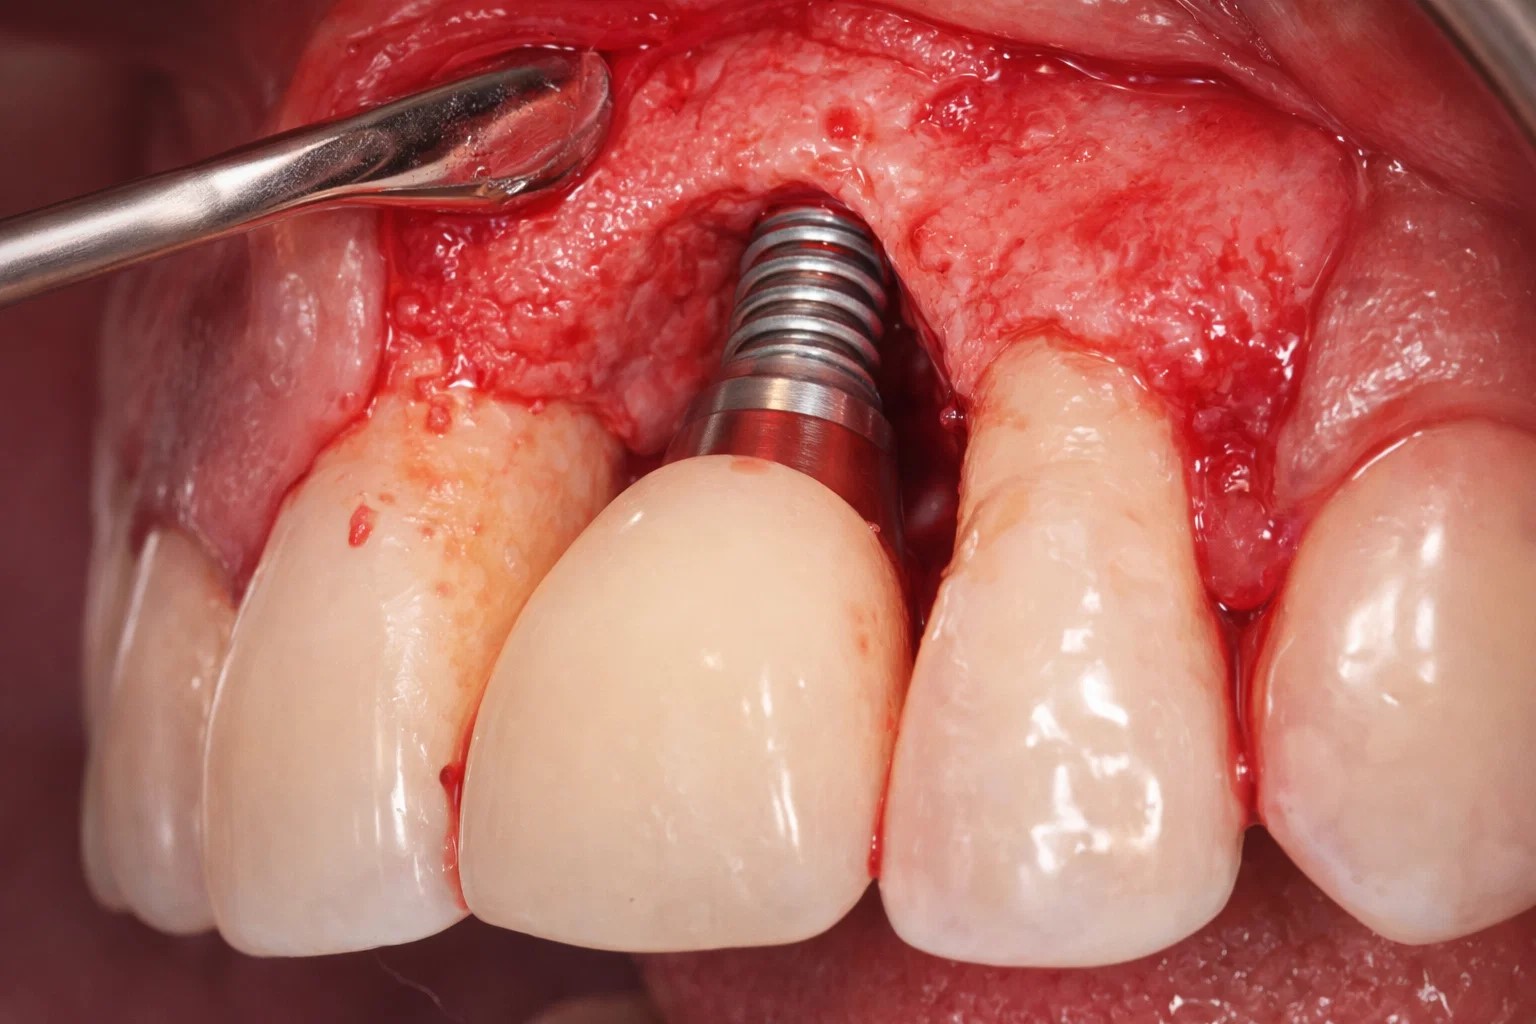

임플란트 후 잇몸 출혈?

방치하면 위험한 ‘주위염’ 신호

임플란트 자체는 인공물이라 충치가 생기지 않지만,

그를 지탱하는 잇몸과 잇몸뼈는 질환에 취약합니다.

양치질 시 피가 나거나 잇몸이 붓는 현상은

임플란트 수명을 갉아먹는 ‘임플란트 주위염’의 초기 신호일 수 있습니다.

임플란트에는 자연치아와 달리 ‘치주인대’라는 완충 조직과 신경이 없습니다.

따라서 염증이 생겨도 통증을 느끼기 어렵고, 세균 침투에 대한 저항력이 매우 약합니다. 피가 나는 증상을 대수롭지 않게 넘기다 보면, 어느 순간 잇몸뼈가 녹아내려 심은 임플란트를 통째로 제거해야 하는 상황이 올 수 있습니다. 통증이 없더라도 정기적인 검진이 필수인 이유입니다.